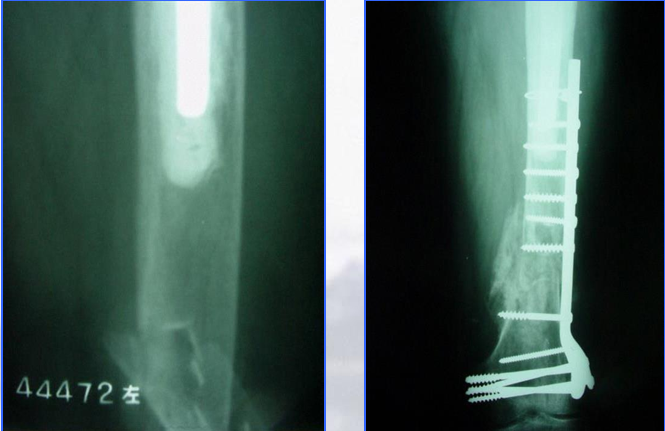

髓外固定:(二)钢板螺丝钉

适用于假体无松动、假体中立位(无外翻)的骨折

成功的关键在于钢板必须和假体末端有部分重叠

假体与钢板重叠部分的固定

环扎方法

特殊钢板

·Ogden钢板 :1988年Zenni :19例 ,17例获得良好临床结果

·Dall-Miles钢板 :2001年Venu :13例 ,10例成功,假体中立位;3例 失败,假体已松动或初始位置为内翻位

·Mennen钢板 :2002年Noorda :36例 ,31%出现了机械固定失败,28%骨折不愈合